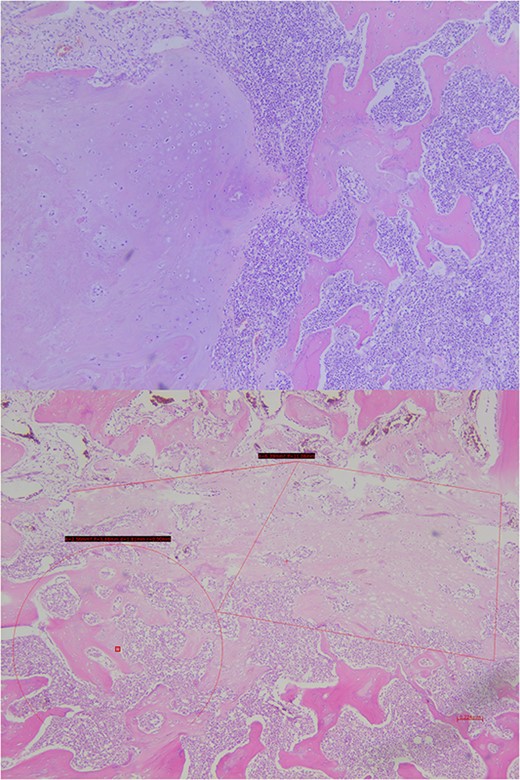

Analysis of the surgical piece established diagnosis of well-differentiated chondrosarcoma (G1) confined to T7 without extension to T6, T8, or soft tissues. Surprisingly, infiltration of high-grade neoplastic component of hematolymphoid type was present. Immunohistochemistry was consistent with DLBCL germinal center subtype (vimentin+/CD45+/CD20+/CD10+/BCL-6+/Ki67 > 80%) (Figs 6–8).

Immunohistochemical study shows how the described hematolymphoid neoplasia presents a immunophenotype typical of B germinal center. CD10+, CD20+, and BCL6+ are showed (from top to bottom).